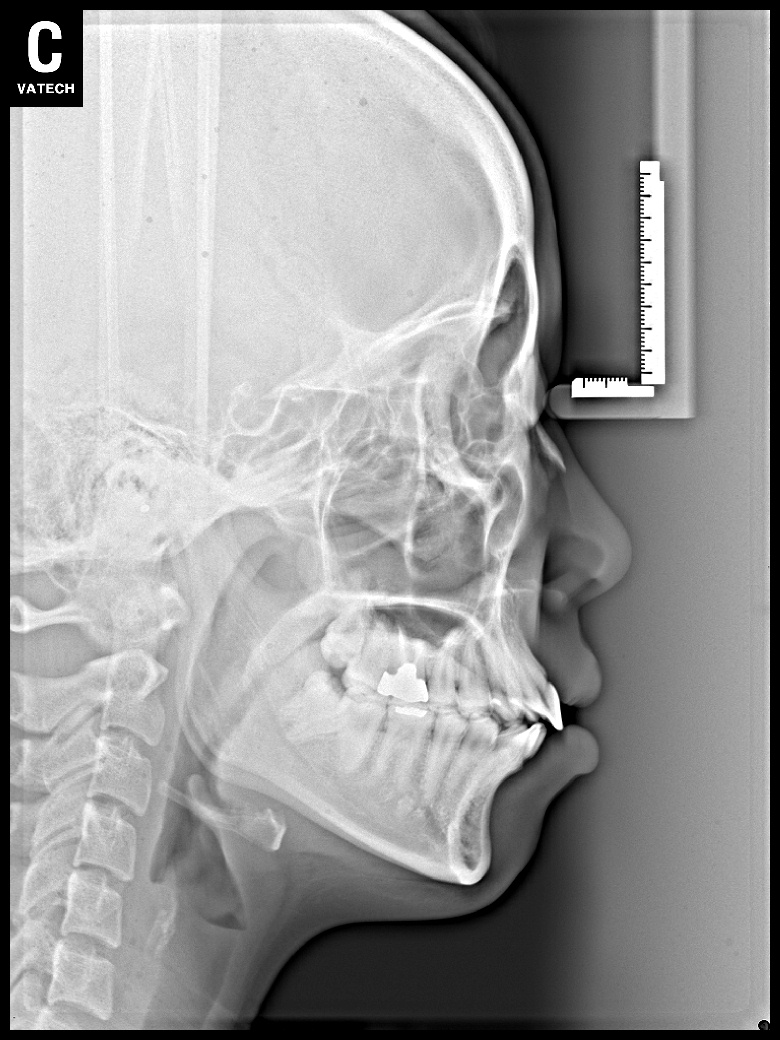

치료 전 사진입니다.